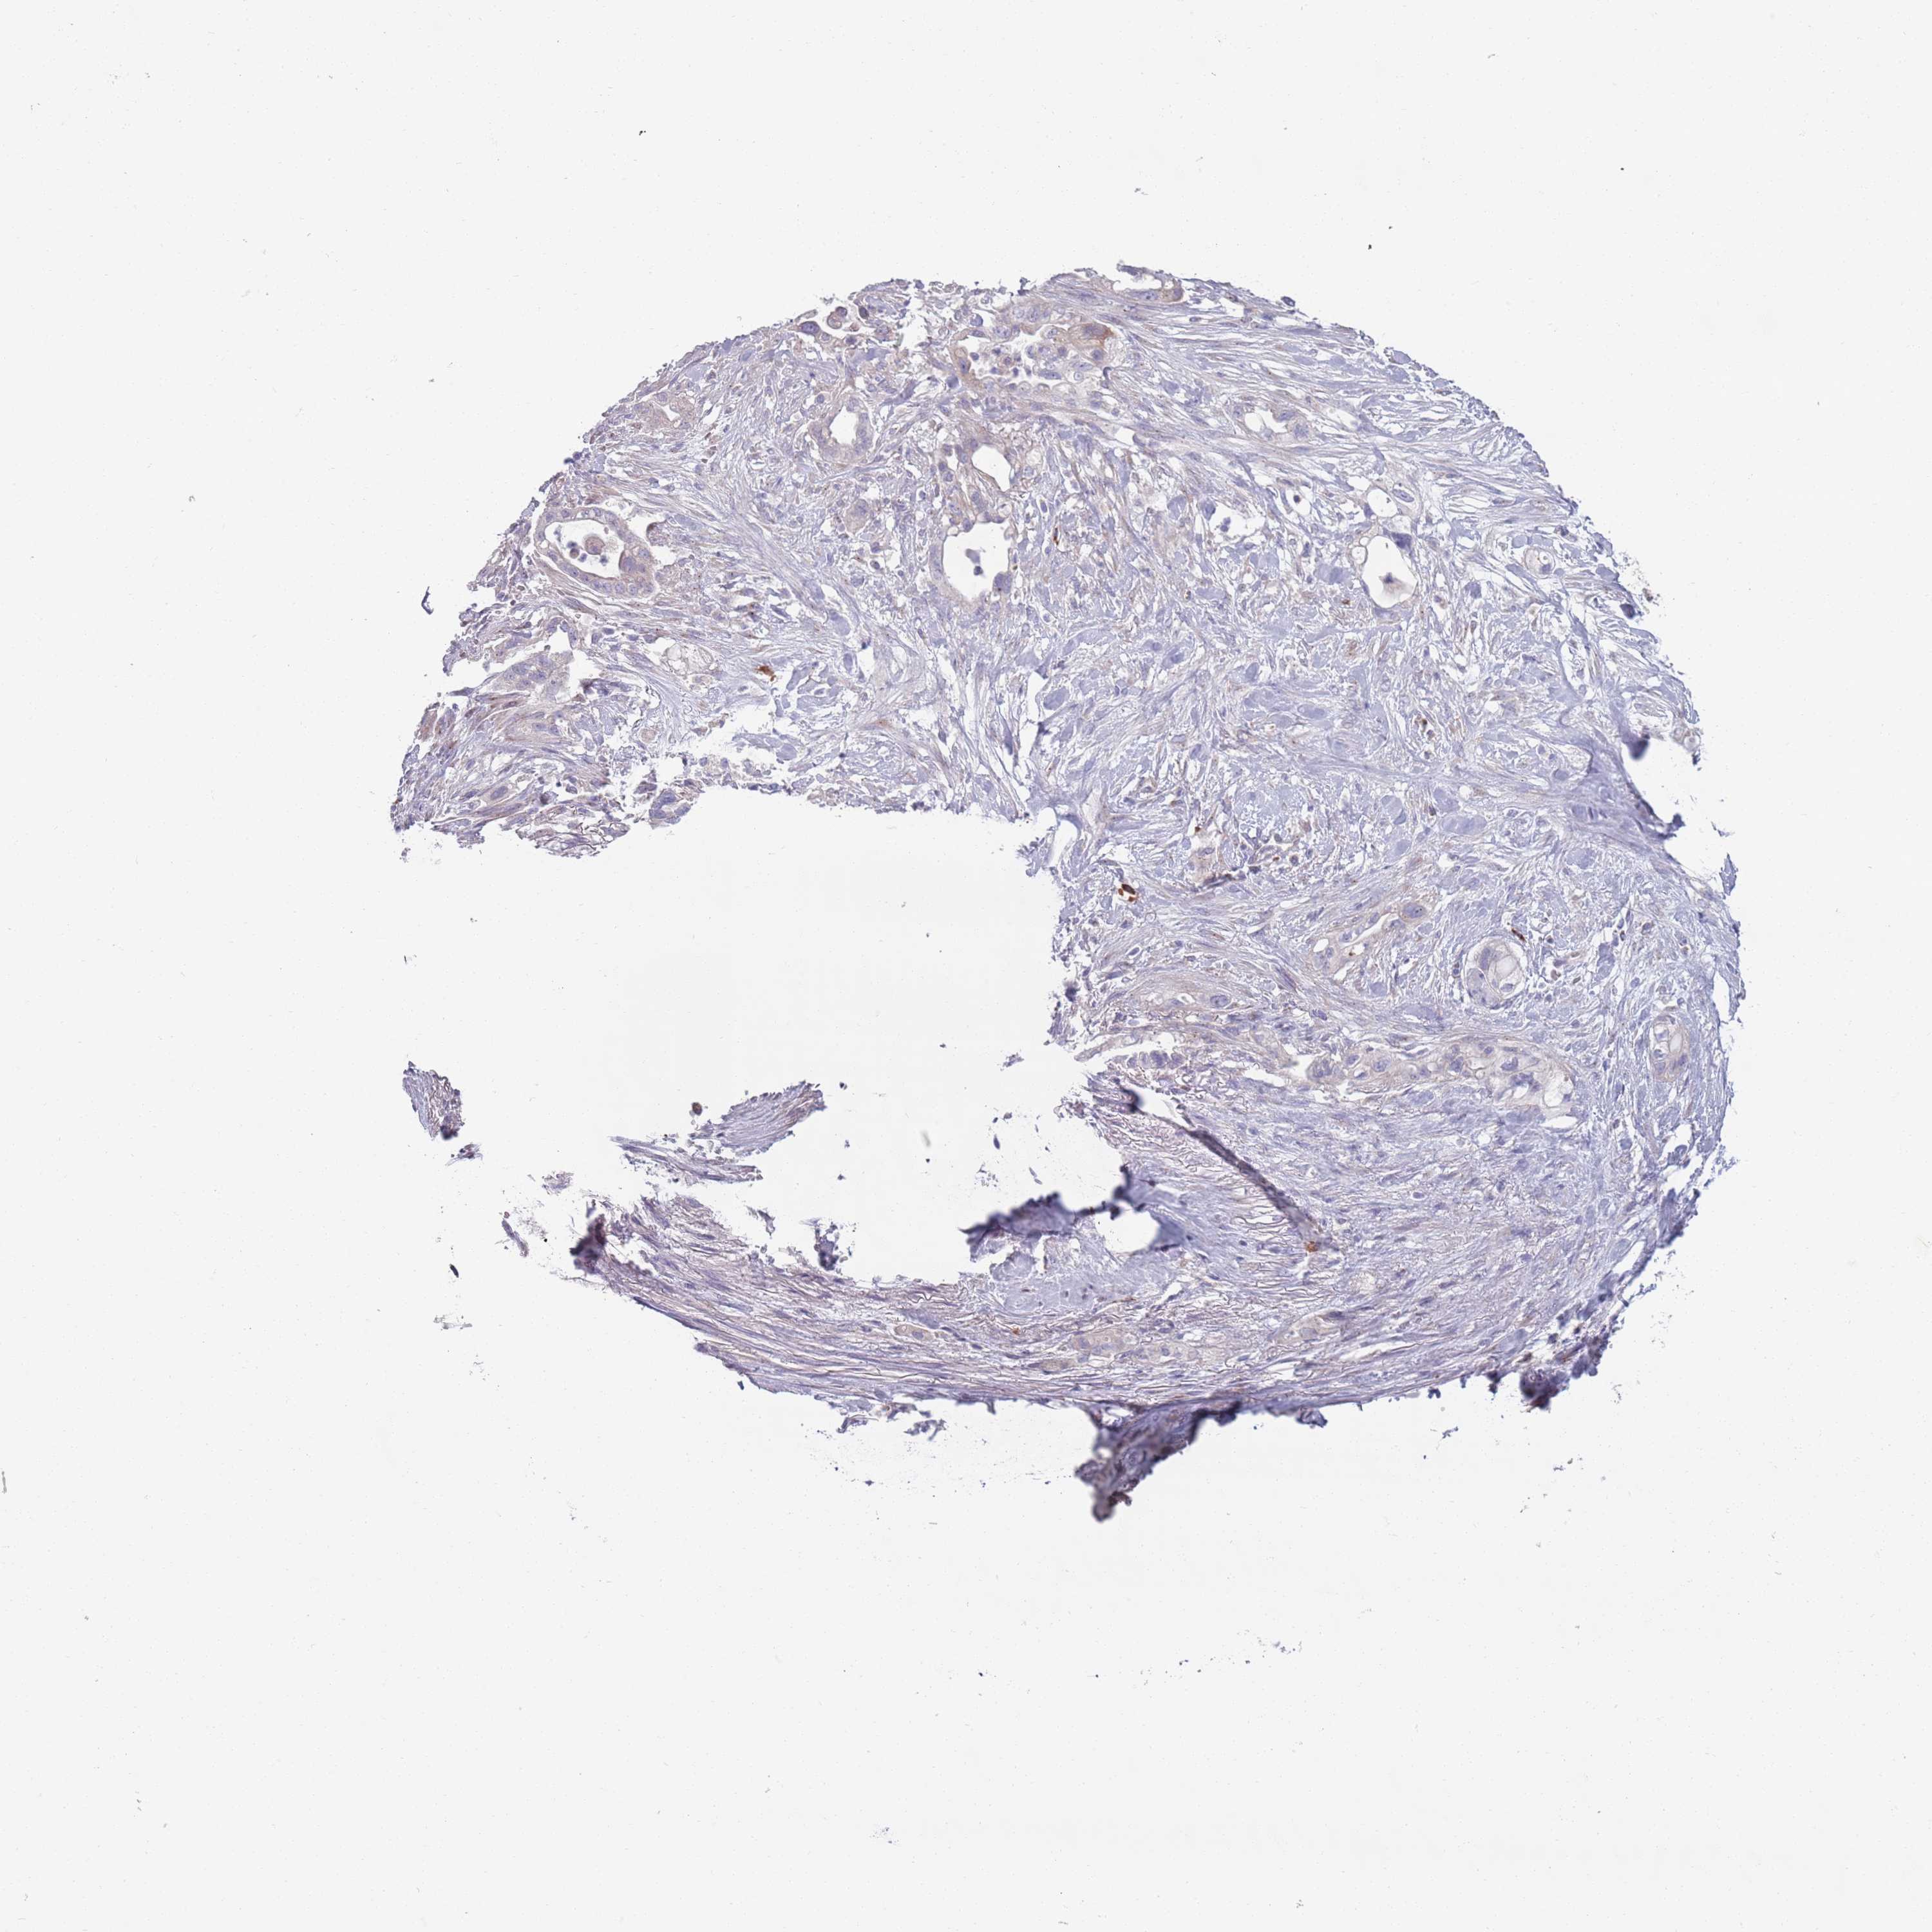

PANCREATIC CANCER - Protein expressioni

A mouse-over function shows sample information and annotation data. Click on an image to view it in a full screen mode. Samples can be filtered based on level of antibody staining by selecting one or several of the following categories: high, medium, low and not detected. The assay and annotation is described here.

Note that samples used for immunohistochemistry by the Human Protein Atlas do not correspond to samples in the TCGA dataset.

Antibody stainingi

Antibody staining in the annotated cell types in the current human tissue is reported as not detected, low, medium, or high, based on conventional immunohistochemistry profiling in selected tissues. This score is based on the combination of the staining intensity and fraction of stained cells.

Each image is clickable and will lead to virtual microscopy that enables deeper exploration of all samples and also displays staining intensity scores, fraction scores and subcellular localization as well as patient and tissue information for each sample.

Antibody HPA048884

Staining

High

Medium

Low

Not detected

Intensity

Strong

Moderate

Weak

Negative

Quantity

>75%

75%-25%

<25%

None

Location

Nuclear

Cytoplasmic/membranous

Cytoplasmic/membranous,nuclear

Adenocarcinoma, NOS